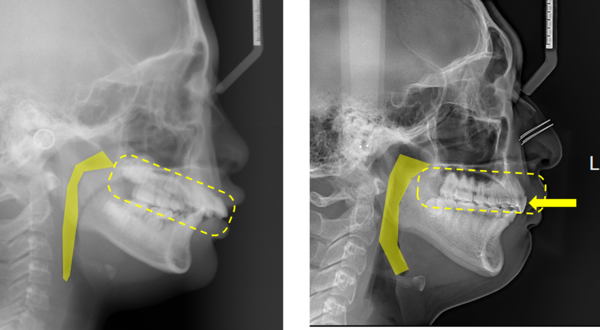

청소년 부정교합 환자들이 치아를 뽑지 않고 후방 이동하는 교정치료를 받으면 부정교합이 치료되는 것은 물론 기도 공간과 골격에도 부정적인 영향이 없다는 국내 연구 결과가 나왔다.

연구팀은 대조군으로 교정치료를 받지 않은 청소년 환자 20명(평균 나이 19.3세)을 선정했다. 치료 전, MCPP 치료 직후, 3년 후의 고화질 치과용 컴퓨터 단층촬영(CT) 이미지를 비교한 결과 MCPP 치료군은 치료 후 유지기간 동안 기도 공간의 유의미한 변화가 없었고 대조군과도 차이가 없었다.

교정치료로 치열이 뒤로 밀리면 기도가 좁아지지 않을까 우려하기 쉬운데 골격에 이상이 없다는 점이 입증됐고 기도 공간이 좁아질 때 생길 수 있는 수면무호흡증과도 무관하다는 점이 확인됐다고 연구팀은 설명했다.

국윤아 교수가 지난 2006년 세계 최초로 개발한 MCPP 비발치 교정법은 이를 뽑지 않고 효과적으로 상악치열을 후방 이동할 수 있는 방법이다. MCPP 비발치 교정법은 특수하게 고안된 골격성 고정장치를 입천장에 고정해 심미적으로 효과가 있으며 환자의 불편함을 최소화했다.